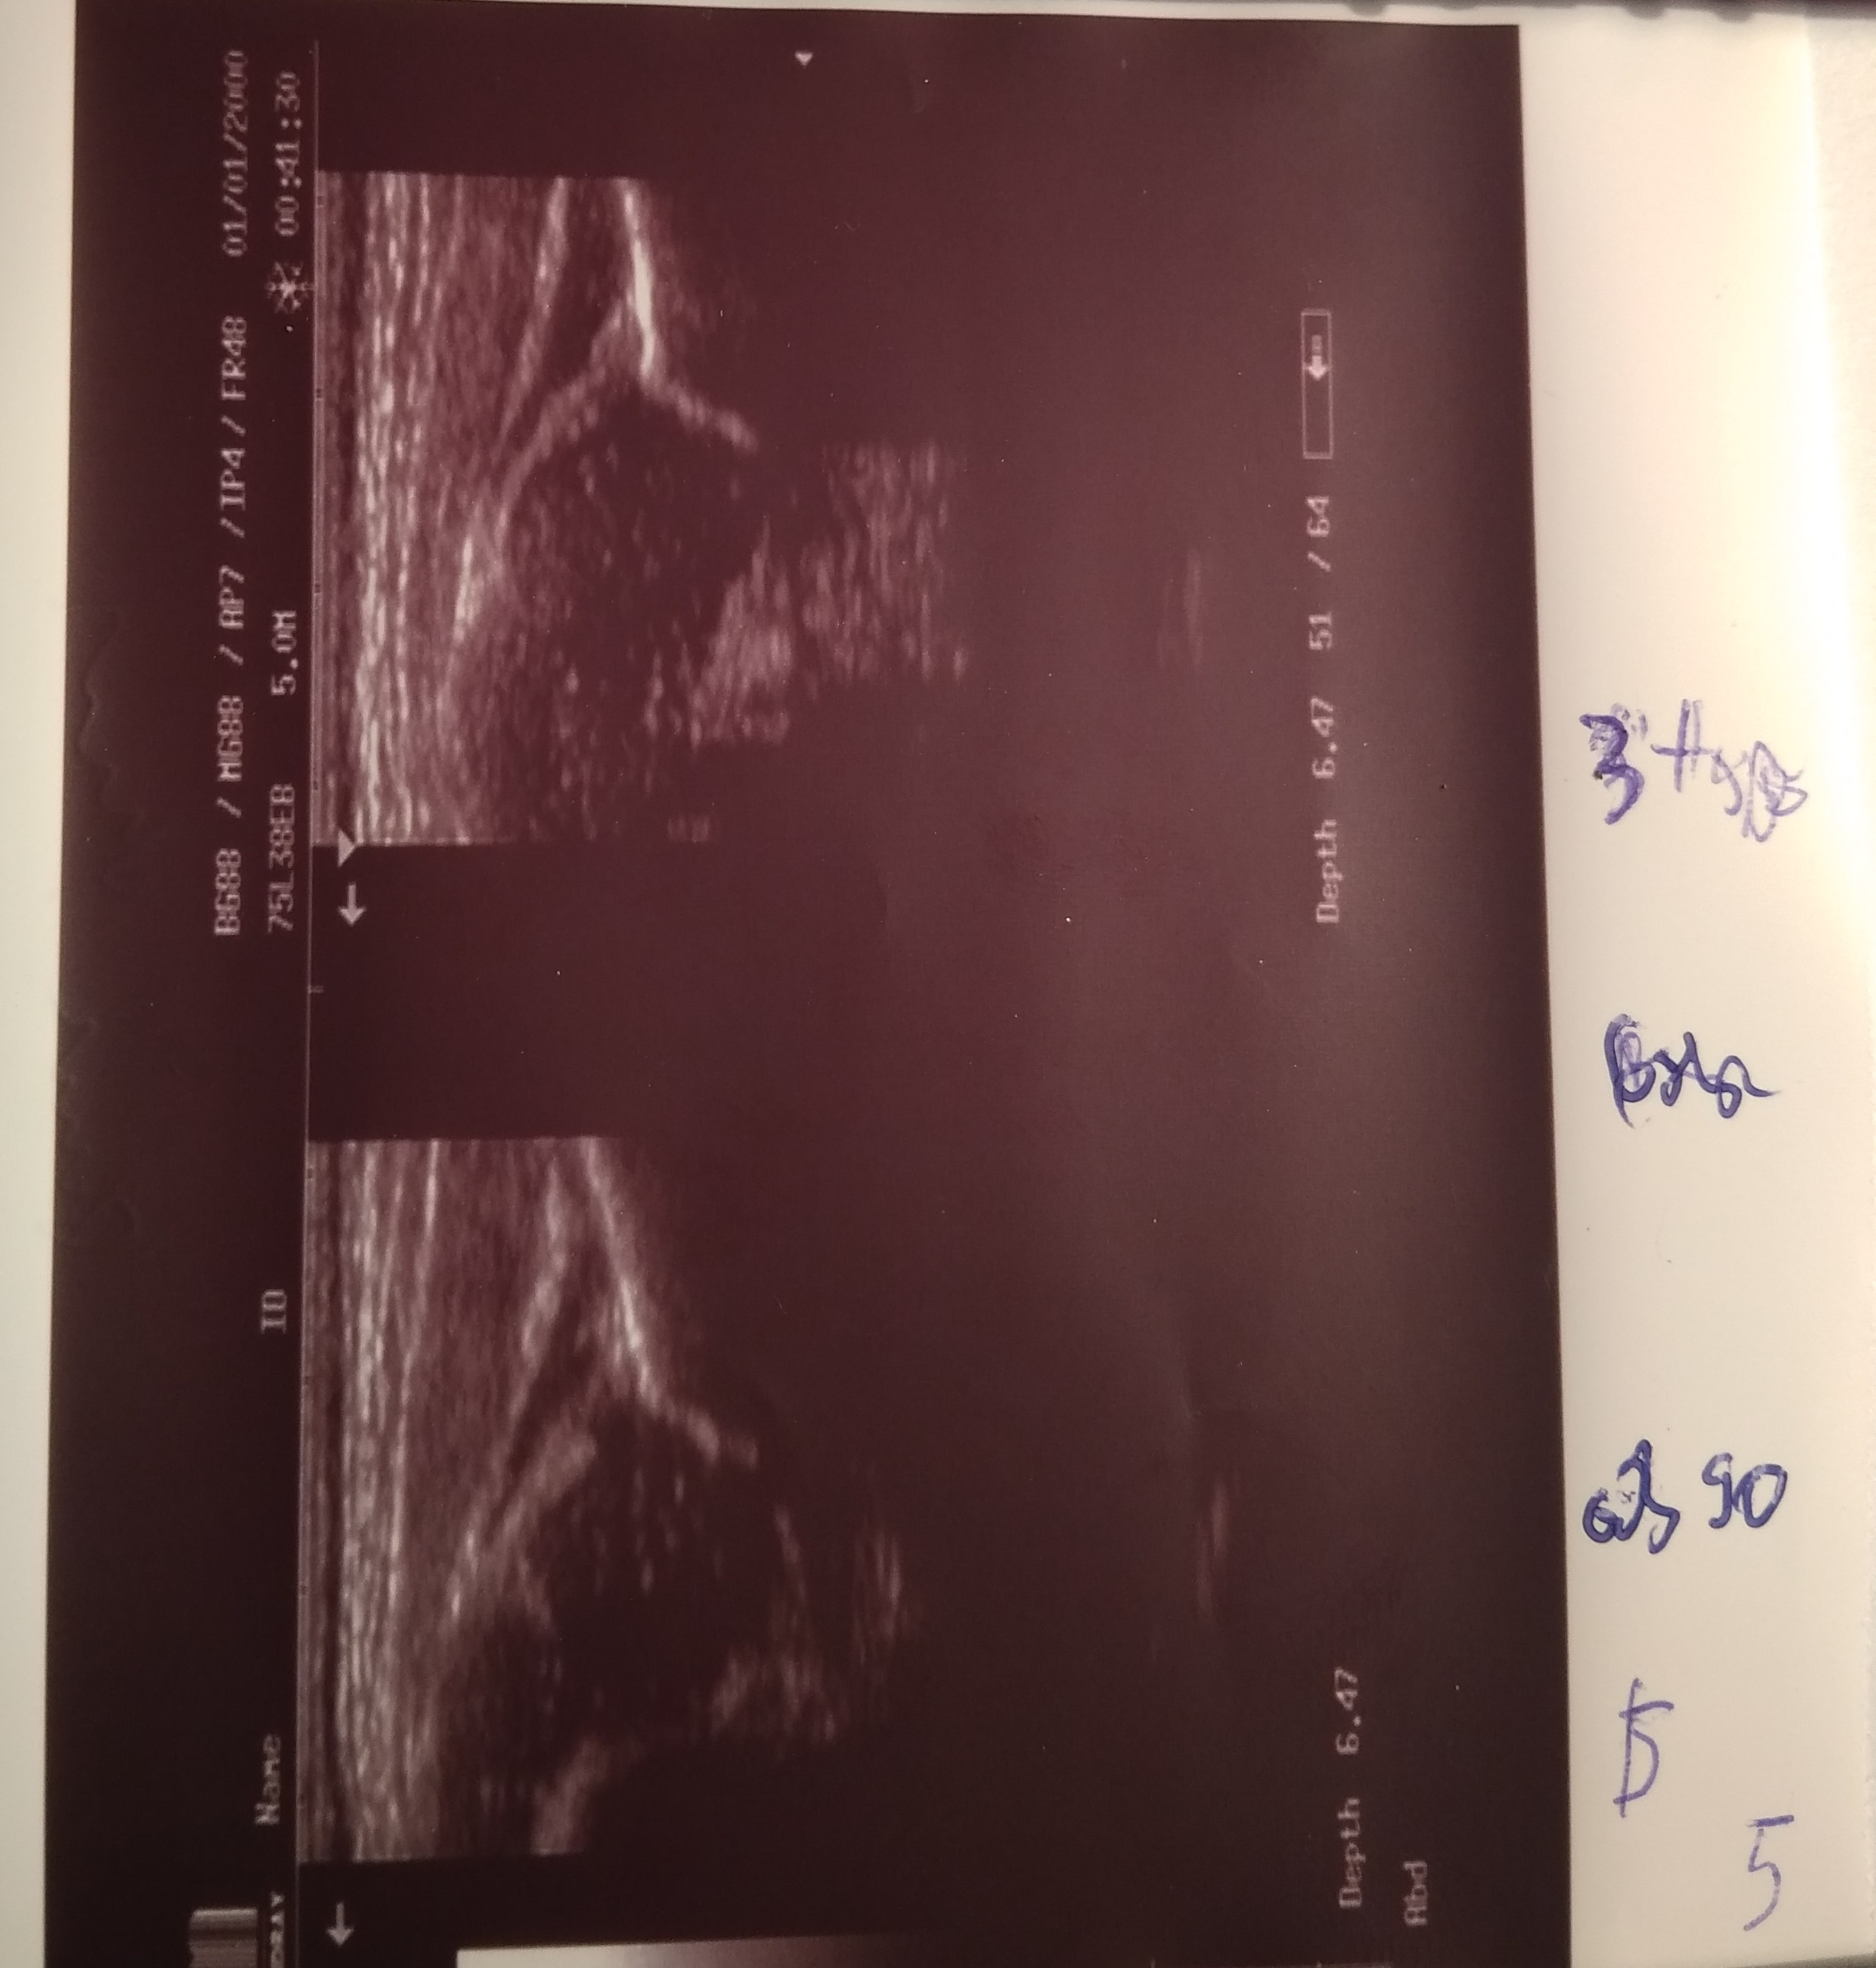

oria Anna 6 dni wtorek

typ P :D L: III/IV biodra niestabilne obustronnie rozpoznana po porodzie na oddziale noworodkowym zlecono usg za dwa tygodnie (brak stadandartów postepowania) ;

przyszła szybciej

profilatyka prowdzona przez rodziców bez przerwy przez całą dobę